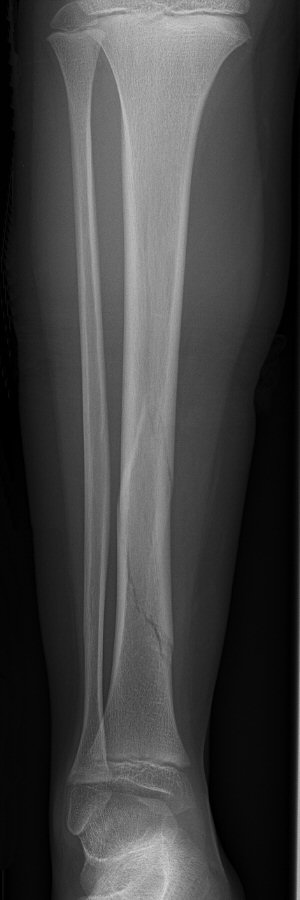

Tibia och fibula-frakturer, tibia spikats med 2 TEN-spik, sista 2 bilderna efter 5 veckor, då inte alls ömmande över frakturerna.